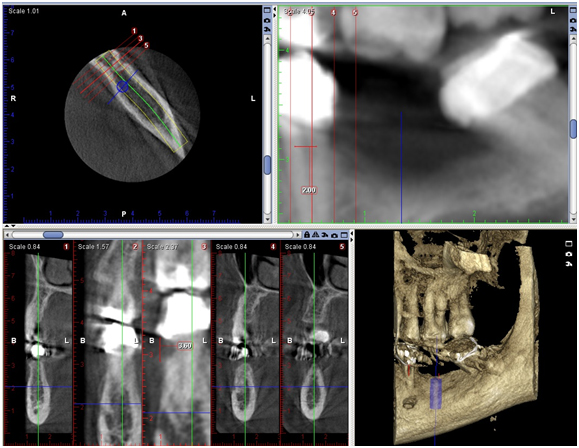

The patient was inquired about the findings in order to know whether she had any sensorial disturbance in the region of the LLQ. She presented no sensorial bilateral disturbance in the regions supplied by the mental nerve. In the panoramic radiograph, the right and left mental foramen (MF) were observable and not relevant to the chief complain, as a normal expected radiolucent area between the left mandibular premolars (Figure 1). For accurate implant placement A CBCT (Appendix 4) images were evaluated in axial, coronal and transversal reformatations (Figure 4), using 1.00 mm slice thickness for implant placement on #36. The image corresponding to the LLQ was clearly demonstrating a depression in the root area above the crestal bone level in the assessed CBCT slices. The measurement of the ICR lesion height and width (3.6/2.0 mm, respectively) was measured using ‘‘distance’’ tool of the software in the most representative CBCT transversal slice (Figure 5).

Figure 4. CBCT images